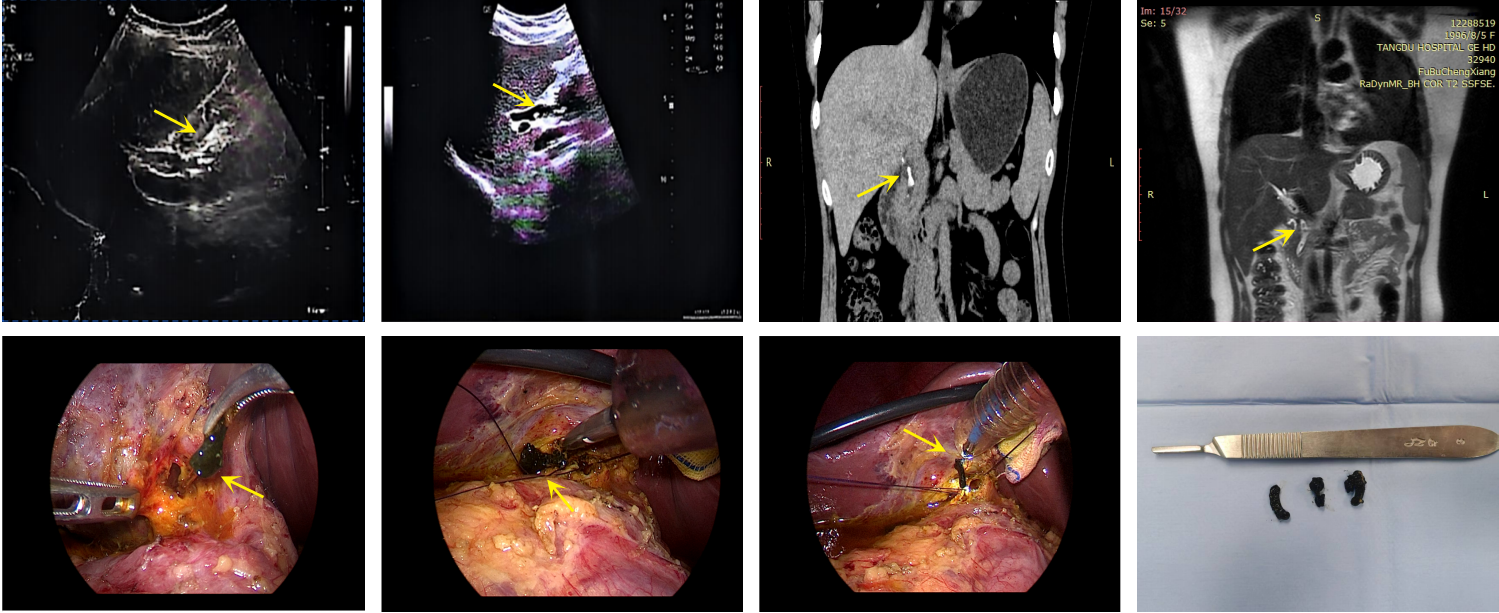

背景与目的 Hem-o-lok夹广泛应用于腹腔镜胆囊切除术(LC)中的胆囊管及血管闭合,但其术后移位虽罕见,却可进入胆总管形成异物,影像学表现易误诊为胆总管结石,增加诊断与治疗难度。针对该远期并发症的识别与处理,临床认知仍有不足。本文通过分析1例相关病例并结合文献复习,总结其临床特征及诊治要点。方法 回顾性分析中国人民解放军空军军医大学第二附属医院普通外科2025年10月收治的1例29岁女性患者的临床资料。患者4年前行LC,本次因体检发现“胆总管结石”1年余入院,术前影像学提示胆总管多发充盈缺损。患者拒绝内镜下逆行胰胆管造影治疗,遂行腹腔镜胆总管探查术(LCBDE),术中确诊为Hem-o-lok夹移位。分析其诊疗过程、影像学特征及术中所见,并结合文献进行讨论。结果 术前影像学提示胆总管多发结石。LCBDE术中经胆道镜探查,于胆总管中下段取出3枚移位的Hem-o-lok夹,周围未见胆色素结石,确诊为“胆总管异物(Hem-o-lok夹)”。术后置T管引流,恢复顺利出院。术后2个月T管窦道造影示胆总管通畅,无残留异物或结石,顺利拔管。结论 Hem-o-lok夹移位是LC术后一种罕见的远期并发症,影像学易误诊为胆总管结石。对有相关手术史的患者,应将其纳入鉴别诊断。LCBDE是确诊及处理该并发症的有效方式。规范术中操作及合理选择闭合方式,并加强术后随访,有助于降低此类并发症风险。

背景与目的 腹腔镜胆总管切开取石术(LCBDE)是胆总管结石的主要微创治疗方式。“单孔+1”腹腔镜技术(SILS+1)在胆囊手术中已显示出微创优势,但其在胆总管切开取石中的安全性与有效性仍有争议。本研究在统一应用吲哚菁绿(ICG)荧光胆管显影及自脱落胆道支架条件下,比较SILS+1与传统多孔LCBDE的围手术期疗效与安全性。方法 回顾性分析2024年3月—2025年3月接受LCBDE治疗的132例胆总管结石患者,根据手术方式分为SILS+1组(n=32)与传统多孔组(n=100)。采用倾向性评分匹配后纳入SILS+1组32例、传统多孔组64例。比较两组术中指标、术后恢复、并发症发生率及美容满意度等。结果 两组手术时间及胆管缝合时间差异无统计学意义(均P>0.05)。SILS+1组标本取出时间更短,切口总长度更小,术后24 h疼痛评分更低,腹壁美容满意度更高(均P<0.001)。两组在术中出血量、住院时间、住院费用及并发症发生率方面差异无统计学意义(均P>0.05)。所有胆汁漏患者经保守治疗恢复,无需再次手术;两组均无残余结石及支架相关并发症。结论 在统一ICG荧光导航及胆道自脱落支架辅助条件下,SILS+1 LCBDE在不增加并发症发生风险的前提下,可进一步减少手术创伤、减轻术后疼痛并改善美容效果,是一种安全、可行的微创手术方式,但其长期疗效仍需进一步研究验证。